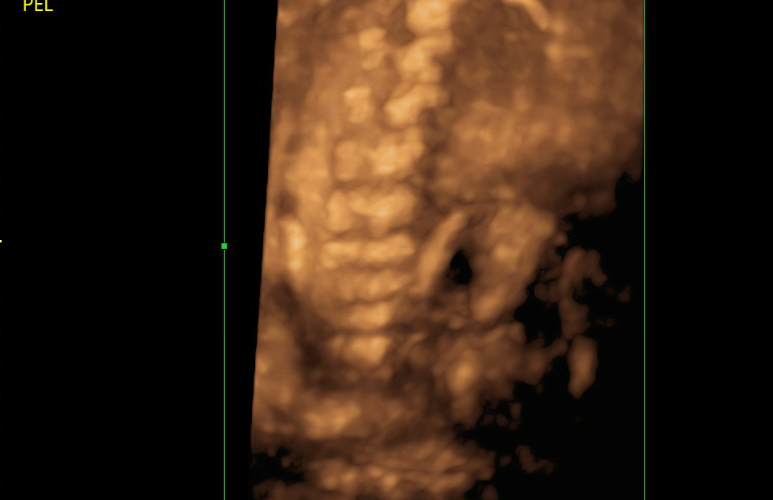

As Anna has Type 4 OI, she had in-utero findings that were monitored by the Maternal Fetal Medicine team. She had demineralization of bones, healing fractures in the femur, bowing of the femurs (but not humeri), and was measuring small for gestational age. It is important to note that she measured small because her long bones are bowed, underestimating their true length, and both her parents are under 5 feet, meaning her interval growth was appropriate but low against the population average.

At each serial ultrasound appointment, the sonographer evaluated existing fractures during and looked for new breaks, particularly in the long bones. It is, therefore, so important to really zoom up the images so that the area of focus takes up 80-90% of the screen, as this can be extremely subtle. The sonographer would also monitor ribs to make sure they were structurally sound and growing properly, as pulmonary hypoplasia is a serious complication.

Demineralization of bones

Intrauterine scoliosis